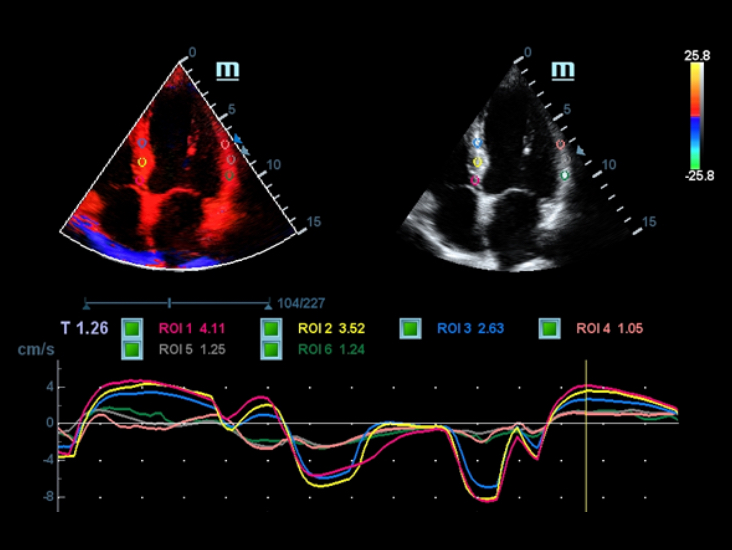

DefiniciĂłn de imagen superior

MĂĄs claridad para el diagnĂłstico

TecnologĂas de obtenciĂłn de imĂĄgenes clĂĄsicas: mejora de la calidad para el diagnĂłstico

Mediante la aplicaciĂłn de tecnologĂas de obtenciĂłn de imĂĄgenes clĂĄsicas, que se migran de sistemas de diagnĂłstico por ultrasonido consolidados, el DC-40 con Full HD le proporciona una mejor calidad de imagen con el grado de detalle que necesita.